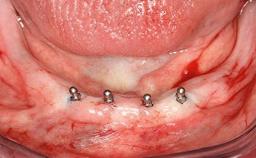

Surgical treatment of a 67-year-old male patient exhibiting an extended edentulous space in the anterior maxilla after the removal of three hopeless incisor teeth.

The video demonstrates implant placement using a surgical stent according to the principle of prosthodontically driven implant placement. The deficient ridge is augmented with locally harvested autologous bone chips, a superficial layer of xenogenic DBBM particles and a resorbable collagen membrane. The surgery is completed with a precise, tension-free primary wound closure.

# of Teeth 4

# of Implants 2

Type of Implants One-Piece